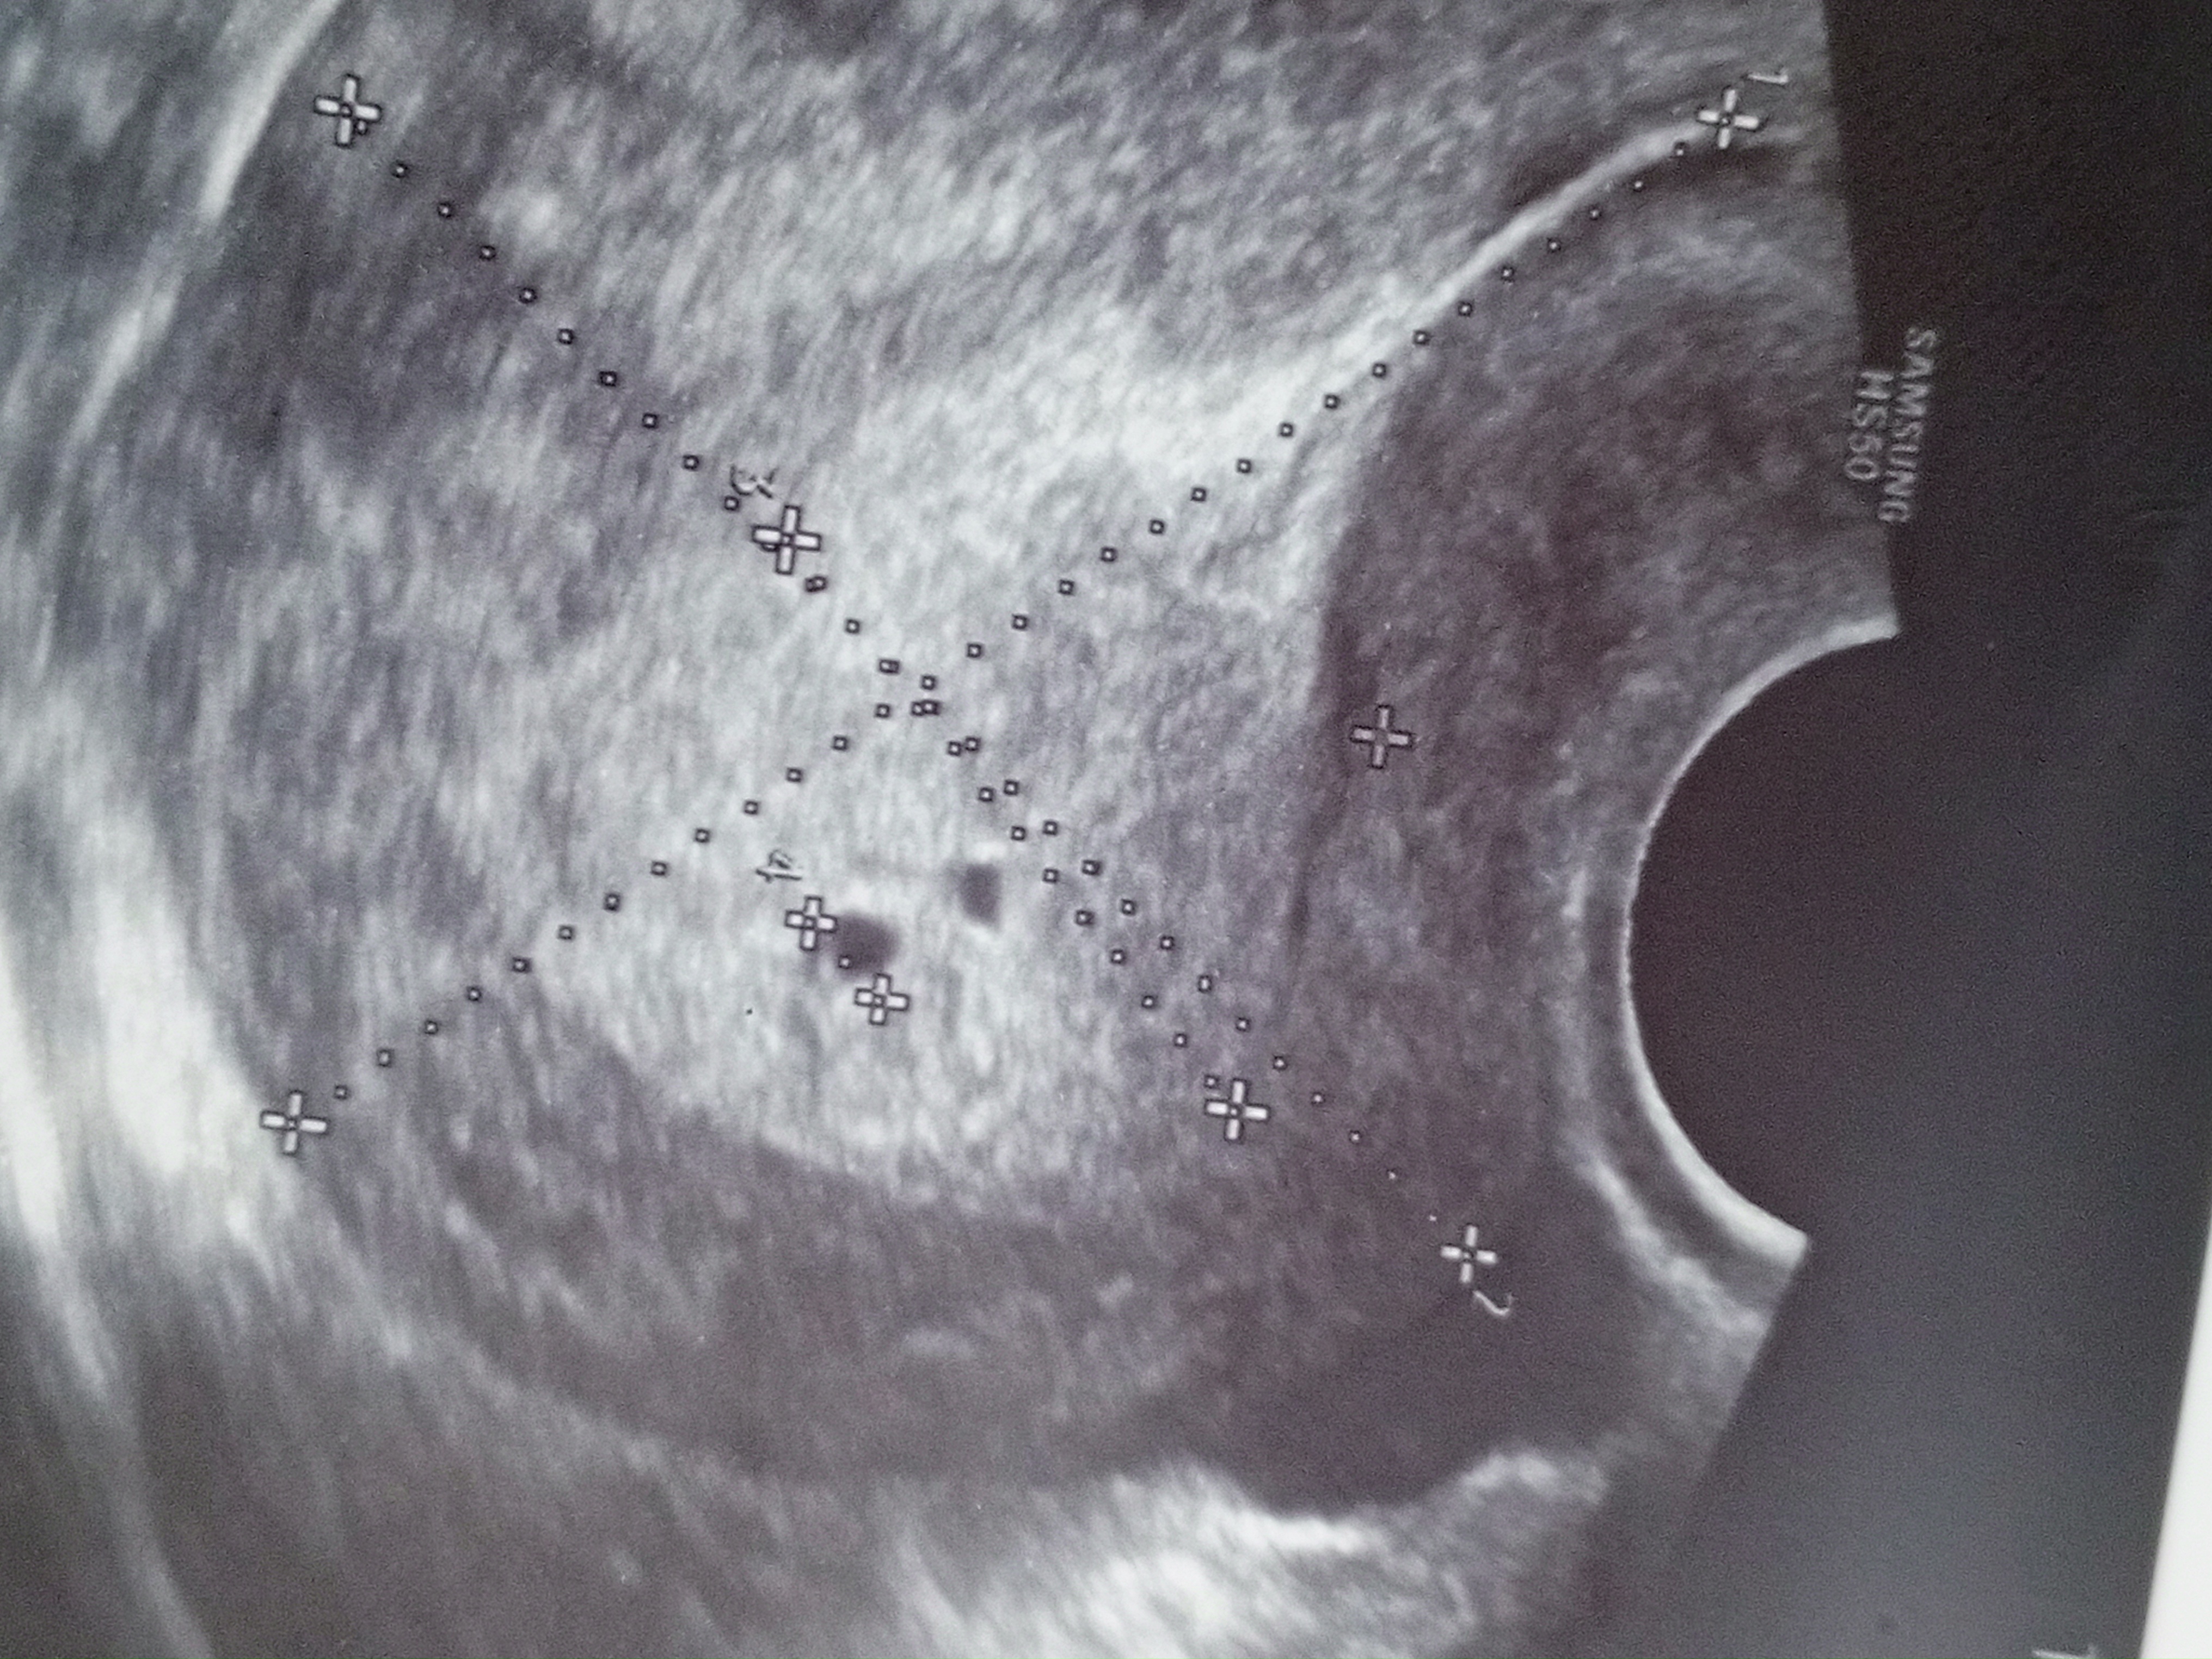

Узи на 20 и 29 дпо

В чем вопрос? Мне если честно не нравится динамика по УЗИ,пя мало выросло и зачатки эмбриона должны уже быть по сроку,29 дпо это уже получается 4,1 от зачатия,значит 6,1 акушерских,а УЗИ у вас на 5 акушерских,я на 29 дпо не ходила на УЗИ,но ходила на 31 дпо,пя 19,ктр 5,4 и ЧСС 146 уд/мин,это в удачную беременность,думаю и на 29 дпо был эмбрион 3 мм и пя около 17 мм,так как он растет по 1 мм в сутки примерно

Марина, за 9 дней, он должен был на 9 мм+- вырасти, я вот на фото посмотрела размер яйца там 1.37см Вот посмотрите, может мне не стоит туда больше не ходить Расст 3 это как раз размер пя Я вот думаю, может она и не захотела искать эмбриончика, говорила типа он прячется Изображение Изображение

Светлана , так здесь несколько размеров,не совсем понятно что и где, вообще считают свд(средний внутренний диаметр)пя,а не одну какую то сторону к примеру пя 12*8*6 свд будет 12+8+6 =26 и разделить на 3 и будет свд 8,6 мм

Марина, все хорошо, нашли эмбриона и сердцебиение 108 уд в мин, пя на 6.1 недель а эмбрион на 5.6 недель все хорошо кроме отслойки, прописали магний, где думали второе плодное яйцо это оказалось ещё одно отслойка, контроль через 10 дней и можно на учет становиться)